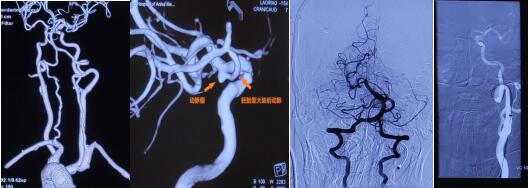

图5、6、7 术中颅内动脉瘤栓塞完全,各相关血管保护良好

术后患者恢复良好,第二天顺利出院